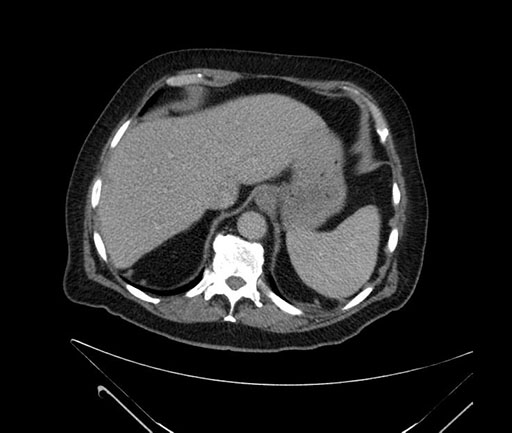

Imaging Analysis

Look through the patient's CT scan to identify any areas of concern for the necessary procedure.

Based on your CT findings, which issue(s) would give reason for "planned slowing down moment(s)" in this case?